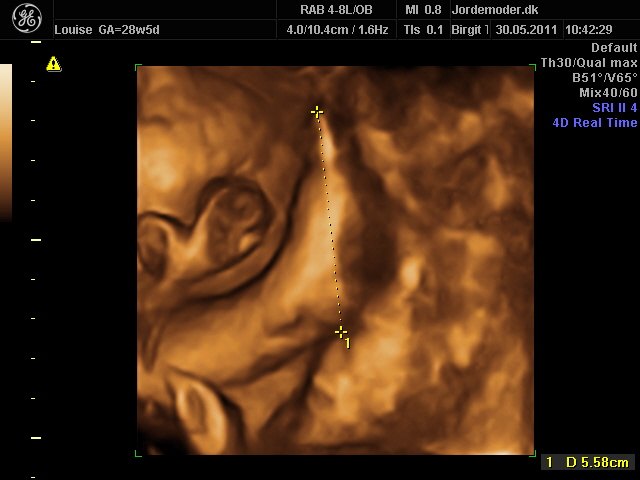

Så kom vi til 3d scanning igår. Lillepigen er slet ikke så stor som egen Jm kønnede hende HELDIGVIS! 1500 gram ca vejer hun nu, 28+6....

Hun har den fineste mund, jeg er helt misundelig på de smukker læber hun har.¨Ja hun er jo alt i alt bare dejlig, og jeg har ikke engang set hende sådan helt rigtig endnu.... Også har hun nogen gode runde kinder....

I skal ikke snydes for billeder af vores lille skønhed...